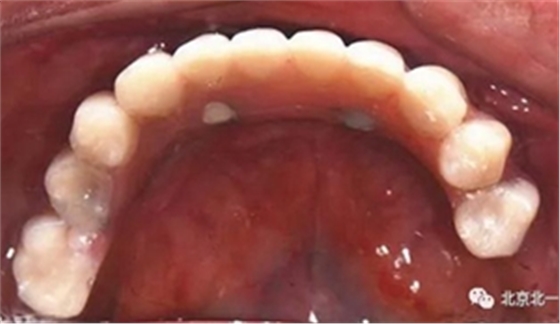

圖十四:口內(nèi)照

圖二十五:口內(nèi)照。